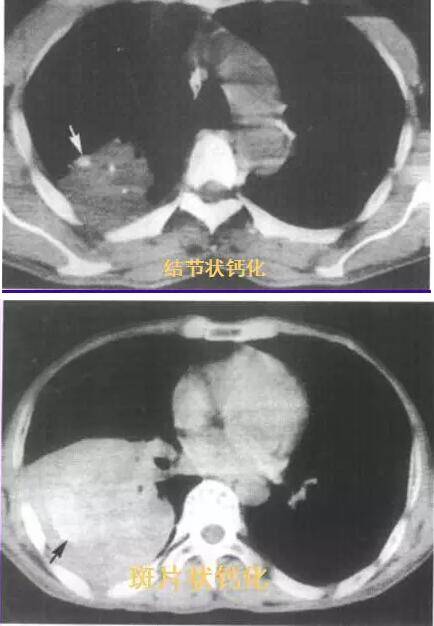

七、钙化

CT检查:发生率为6-7%,斑片状钙化位于肿瘤中心, 肿瘤坏死后发生;结节状钙化多位于周边,肿瘤将原有钙化包裹所致。